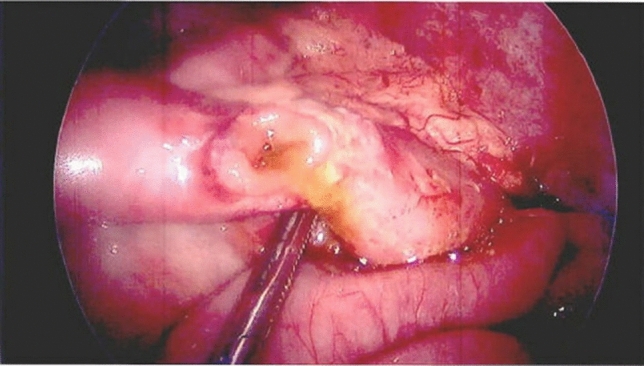

Methods and procedures: An 81-year-old Caucasian female was admitted to the emergency room with a complaint of 24-h epigastric pain, associated with nausea. She had history of a laparoscopic reduction of the foramen of Winslow internal hernia in our institution. CT scan of her abdomen showed a lesser sac internal hernia with an incarcerated colon and underwent a laparoscopic repair with a flap of falciform ligament and laparoscopic cecopexy. The surgery was successful.

Results: Foramen of Winslow hernias, a rare type of internal hernia. Internal hernias have an incidence rate of less than one percent, with Foramen of Winslow hernias accounting for only 8% of all internal hernias. The case at hand involves an 81-year-old Caucasian women who described a prior history of hypertension and a past laparoscopic reduction of the Foramen of Winslow internal hernia in the past. She had complaints of 24-h epigastric pain associated with nausea. She underwent a CT scan of her abdomen which revealed a lesser sac internal hernia with an incarcerated colon and was taken to the operating room where her Foramen of Winslow internal hernia was repaired laparoscopically using a flap of falciform ligament. The hernia contents included the ascending colon and ileum and were viable. A laparoscopic cecopexy and a flap of falciform ligament were done. The surgery was successful.

Conclusion: Foramen of Winslow internal hernias are exceedingly rare, as they account for approximately 8% of all internal hernias, which themselves have a precedence of less than 1%. Despite limited occurrence of Foramen of Winslow hernias, these hernias have mortality rates as high as 49%. Once diagnosed, several methods for repairing Foramen of Winslow hernias have been described. As surgical equipment and technology continue to improve, many surgeons have been switching from laparotomies to a laparoscopic approach. When the cecum shows signs of excessive movement, a cecopexy is often performed laparoscopically to limit such movement. In addition to cecopexy, a flap of falciform ligament was created in order to obliterate the space into the Foramen of Winslow. This novel approach has not been described in the literature. We strongly believe that it should be included as an option to treat these difficult hernias in the future.